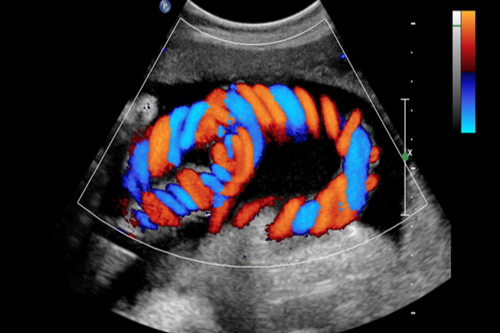

Color Doppler

What is a Color Doppler ?

A Doppler ultrasound is a diagnostic imaging test utilizing sound waves to assess blood flow within your blood vessels. It can examine blood circulation in various parts of your body, including organs, neck, arms, and legs.

This type of ultrasound evaluates both arteries (which carry oxygen-rich blood from the heart and lungs to the body) and veins.